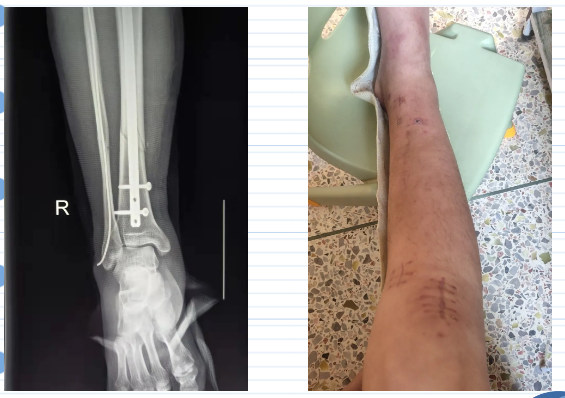

患者李某,男,37岁,因“摔伤致右小腿疼痛约两小时”于2021年9月20日13:09来诊,平车推行入院。缘患者2021年9月20日约11点,在工作时从约两米高处梯子上失足摔伤致右小腿疼痛不适,肿胀,活动障碍,无右下肢感觉异常,无头晕、恶心呕吐,无心悸、胸闷,由他人送至我院急诊外科就诊查x片提示“右胫腓骨中下段骨折”,为进一步治疗而收住院,入院诊断为:“1.右胫骨骨折 2.右腓骨骨折 3.左肘挫擦伤”。

入院后杨为民副总院长查看病人后诊断该患者为:“1.右胫骨骨折 2.右腓骨骨折 3.左肘挫擦伤”,指示先予完善相关辅助检查,患肢夹板及肢具外固定,吸氧、心电监护,密切观察病情变化,经充分抗炎对症消肿治疗后,做好术前准备。于2021年9月20日14:30送手术室在腰硬联合麻下、C臂机下行“右胫骨骨折闭合性复位空心髓内钉内固定术+右腓骨骨折闭合性复位弹性髓内钉内固定术”手术取得圆满成功。该术式手术创伤小,外观美观,术后恢复快。术后患者在外科病区团队精心护理及康复治疗下,患者恢复情况良好。